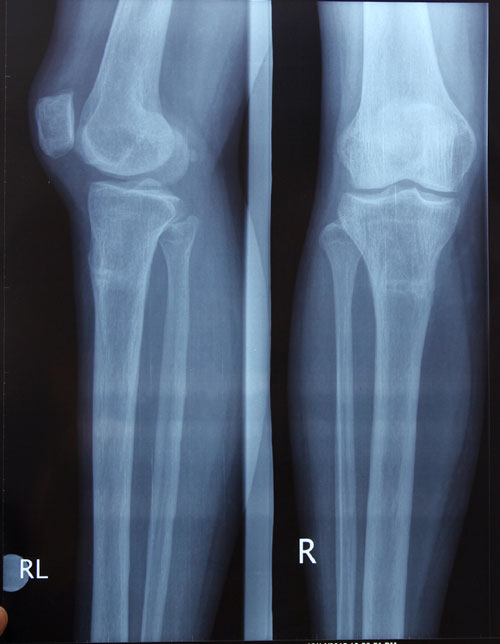

рентген контроль в 1,5 месяца после снятия аппарата.

По результату рентгена - Вам разрешено всё без ограничений (спорт, каблуки, нагрузки). Кроме: беременности в течении первых 6 месяцев после снятия аппаратов.